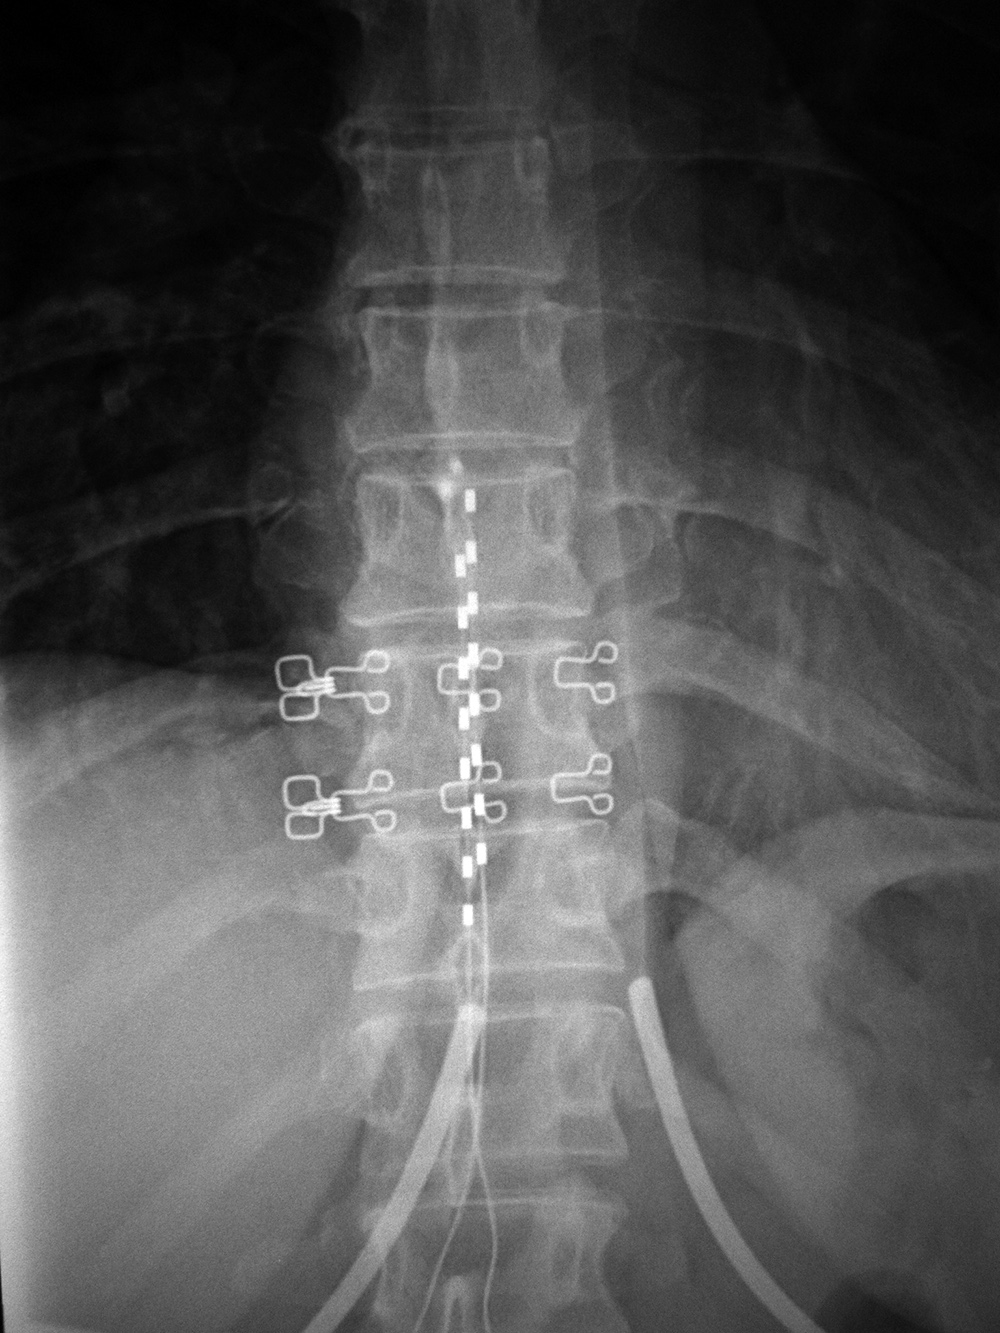

A battery pack overlies the right 12th rib. Wires are going to the bilateral bony fusion masses. There is a laminectomy from L2 to L5 with bilateral pedicle screws and a pedicle plate on the right and a connecting rod on the left. Brantigan vertebral cages are at the L5-S1 disk space. From Hunter, 2004 |